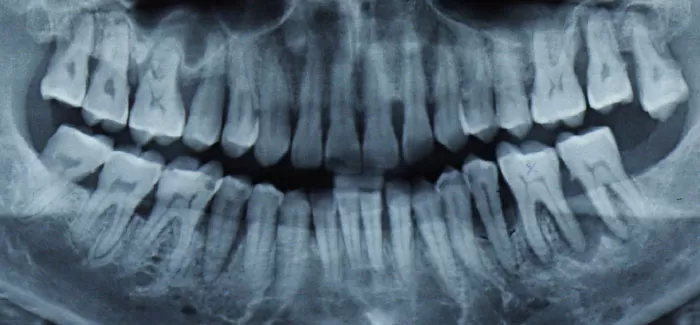

The patient above was diagnosed with generalised moderate to advanced chronic periodontitis. The treatment plan involved 3 sessions of subgingival debridement under local anaesthetic. Biofilm removal was carried out using EMS Airflow and Perioflow. Supra and sub gingival calculus was removed using EMS Piezo ultrasonic instrumentation including the slim-designed PS and P tips. Finally residual deposits were removed with Hu-Friedy curettes.

The patient was successfully treated and is now on a strict program of periodontal on a 3-4 monthly basis.